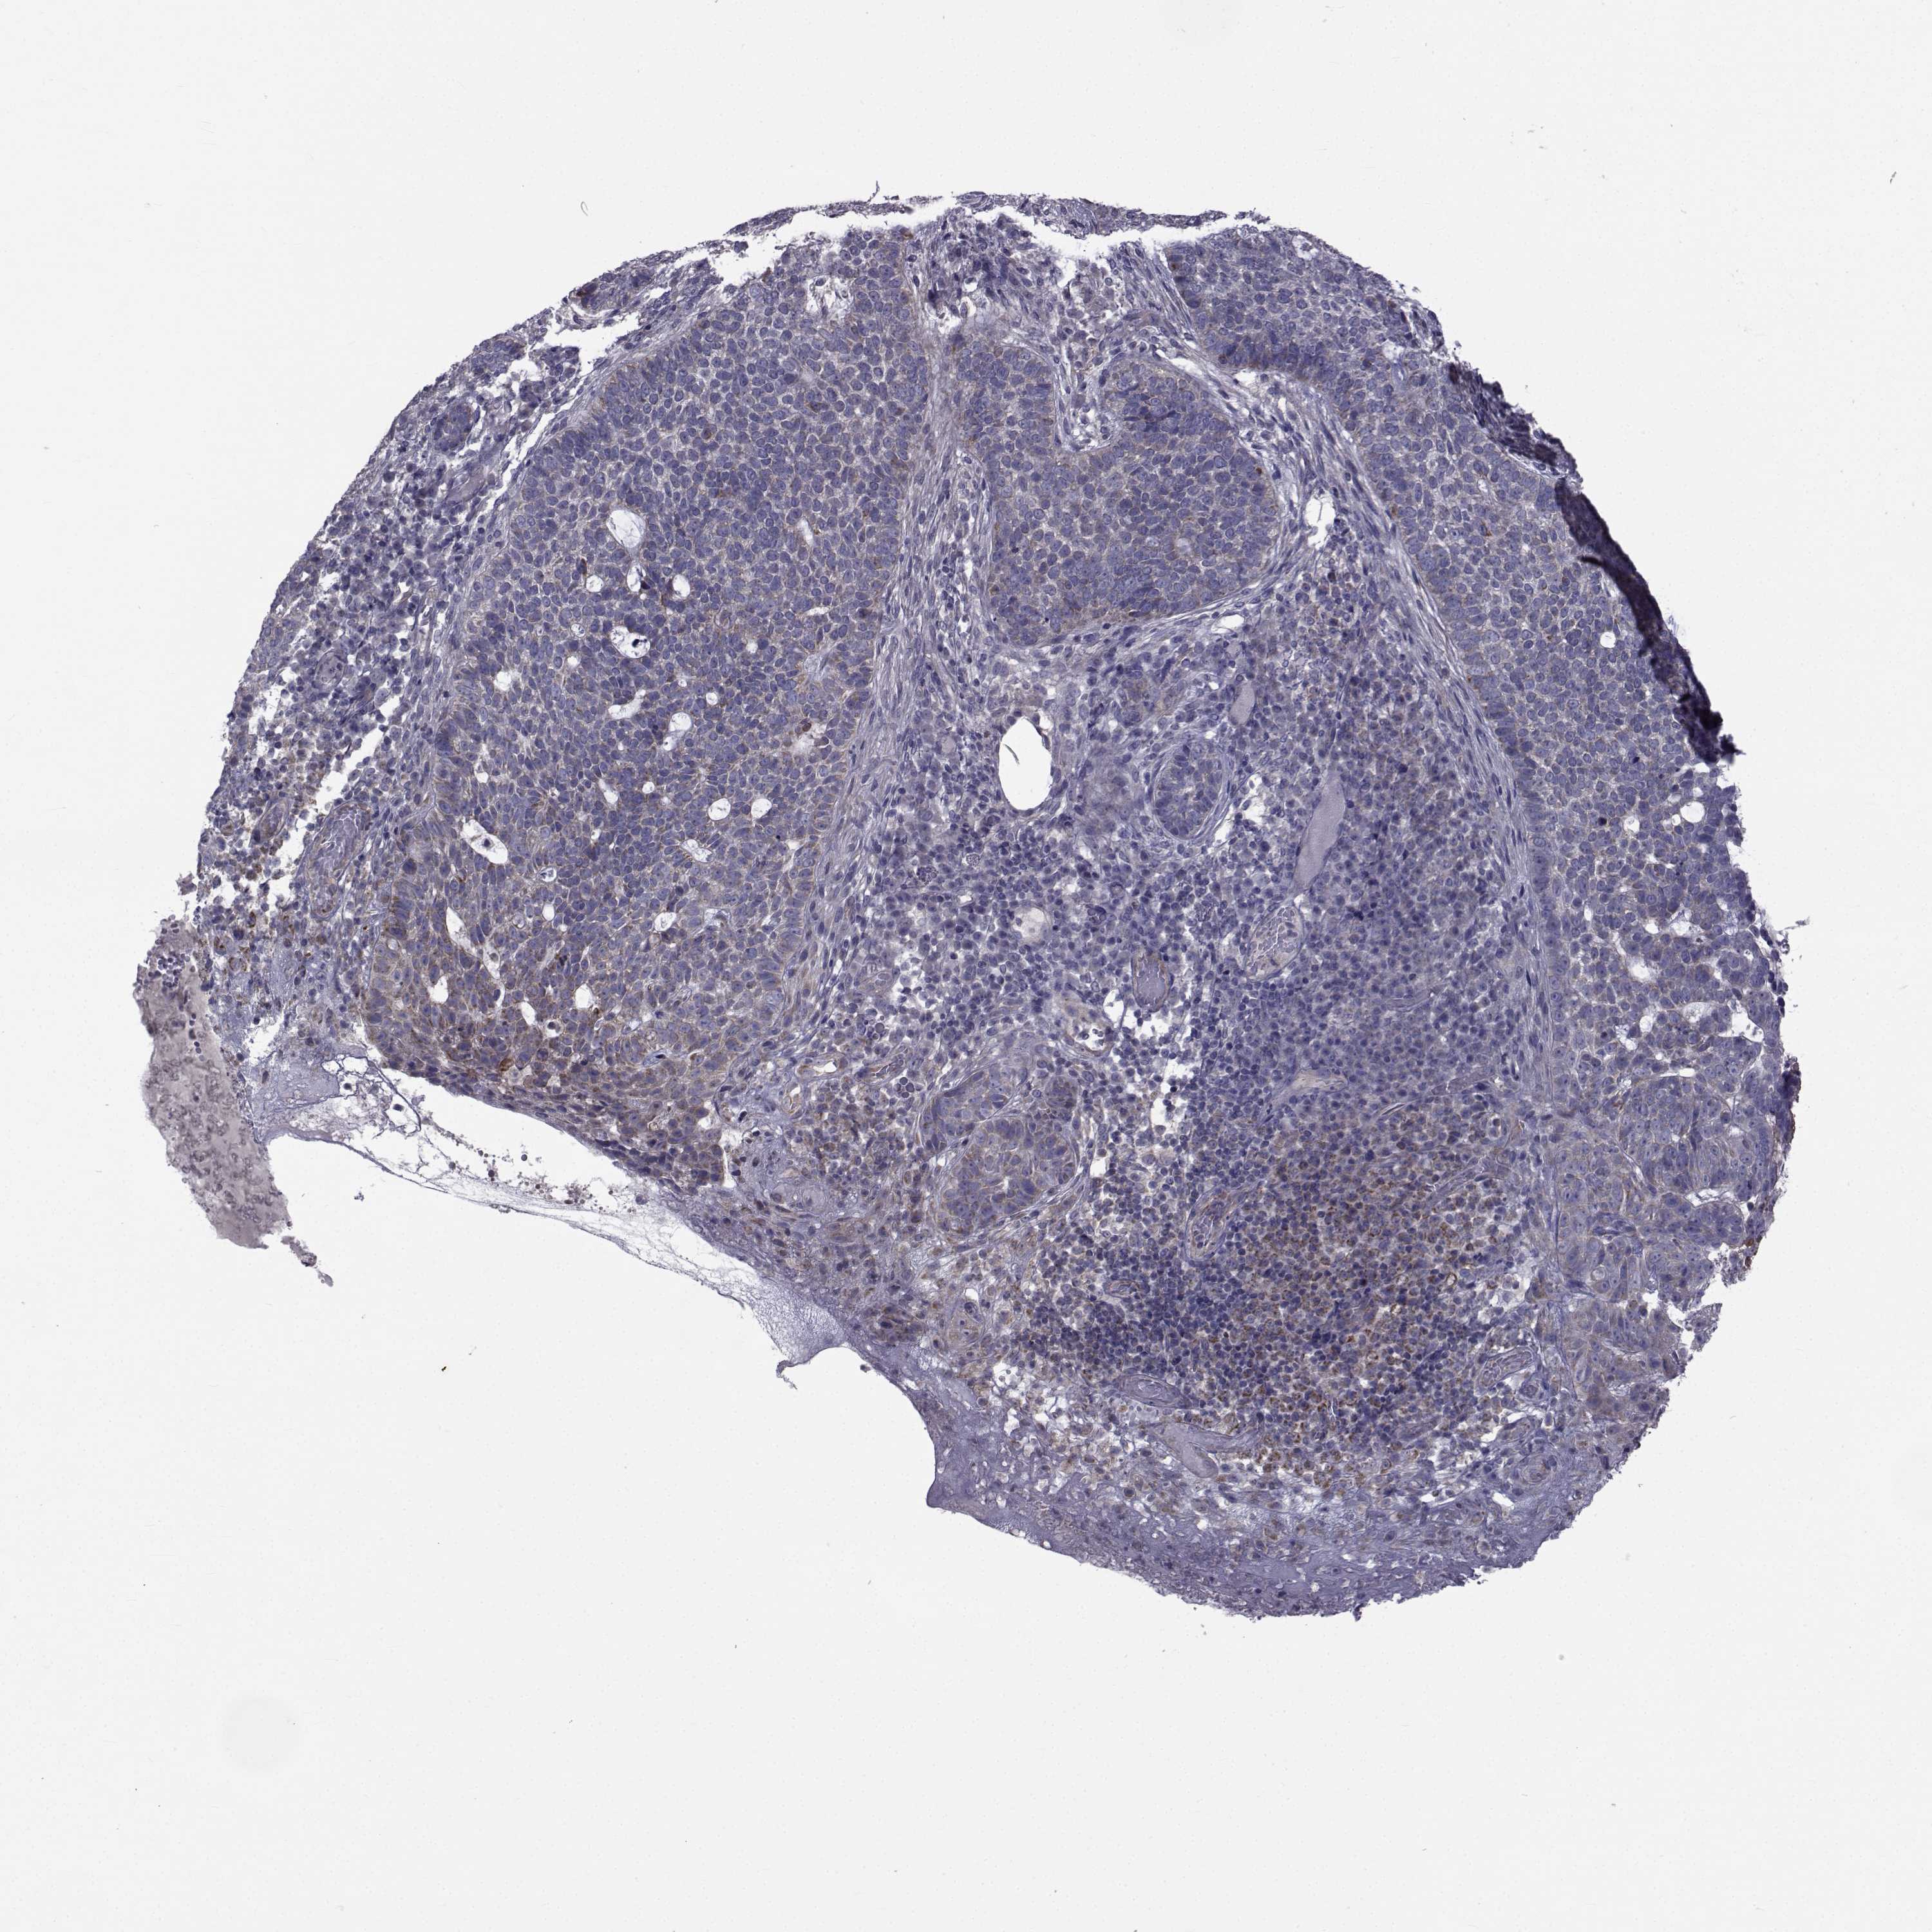

CANCER SKIN CANCER Show tissue menu

SKIN CANCER - Protein expressioni

A mouse-over function shows sample information and annotation data. Click on an image to view it in a full screen mode. Samples can be filtered based on level of antibody staining by selecting one or several of the following categories: high, medium, low and not detected. The assay and annotation is described here.

Each image is clickable and will lead to virtual microscopy that enables deeper exploration of all samples and also displays staining intensity scores, fraction scores and subcellular localization as well as patient and tissue information for each sample.

Antibody HPA028521

Antibody HPA029274

Antibody HPA030240

Basal cell carcinoma